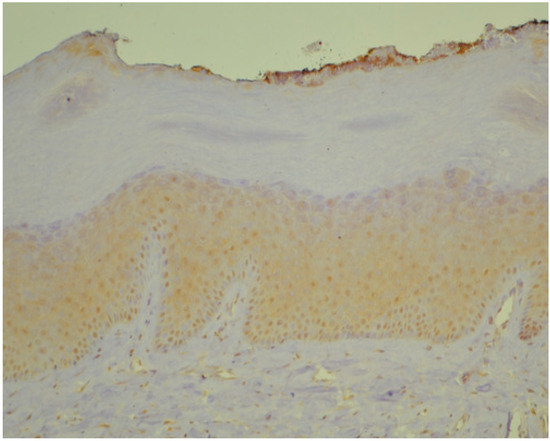

2.2. Histopathology and Immunohistochemistry

3.1. Histopathology and Immunohistochemistry